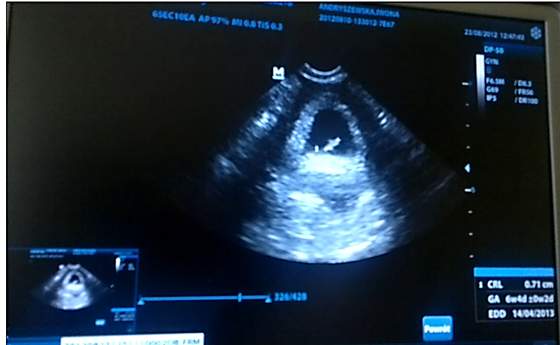

A ja zdecydowałam się w końcu dodać suwaczek